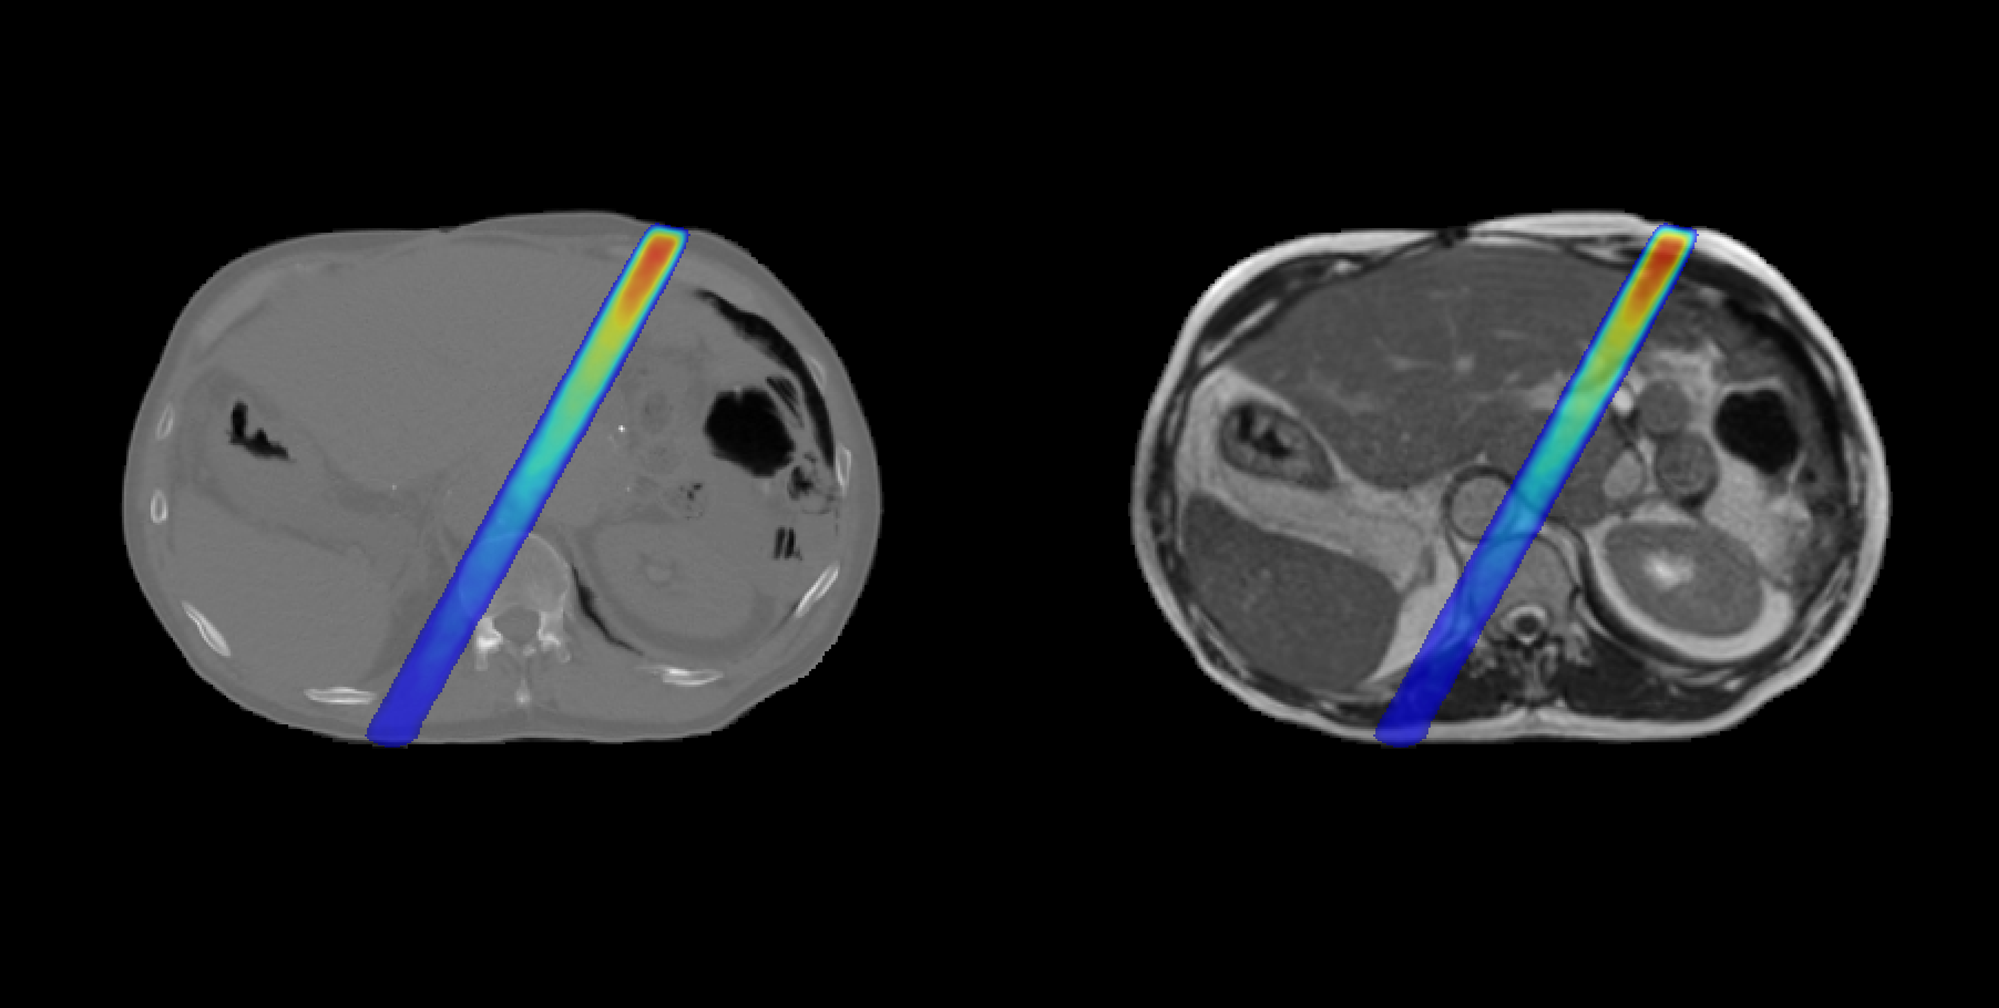

DoseRAD2026 aims to benchmark state-of-the-art methods for fast and accurate radiation dose calculation, for both photon and proton radiotherapy, using either computed tomography (CT) or MRI as input.

The challenge consists of four tasks reflecting current and emerging radiotherapy technologies:

-

Proton dose calculation on CT

Required for high-precision proton therapy planning, where accurate modeling of particle transport is essential due to the sharp distal fall-off of proton beams. -

Proton dose calculation on MRI

Supporting MRI-only proton therapy workflows and future developments in MRI-guided proton therapy.